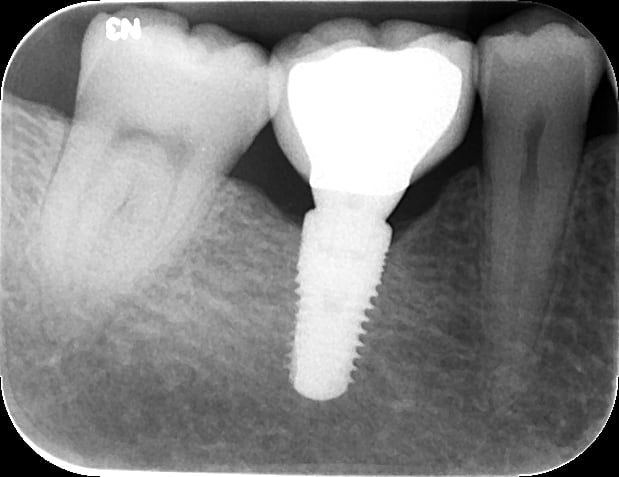

A high implant stability quotient (Osstell® ISQ = 80) (Osstell, www.osstell.com) and insertion torque values >50 Ncm allowed the prosthetic phase to begin in April 2012 (Visit 3). Figure 44 shows the periapical radiograph at Visit 3; Figure 45 shows good healing and tissue tone at this visit as well.

Figure 50 shows the final periapical view of the osseointegrated implant, abutment, and final screw-retained PFM crown at the 18-month follow-up (Visit 7). Bone loss of 1 mm to 2 mm is radiographically apparent around the implant in this view, as compared to 2 months post-implant placement (Figure 44). However, this is likely of little or no clinical significance, because no PD recorded at 18 months exceeded 3 mm (Table 6). The process by which this bone loss probably occurred is discussed below.